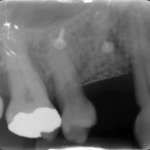

Rigenerazione perimplantare con sostituto osseo e membrana corticale di origine equina un caso... Premium

Viene presentato un caso clinico in cui sono stati utilizzati un innesto osseo equino in forma granulare e una membrana corticale, anch’essa ottenuta da...